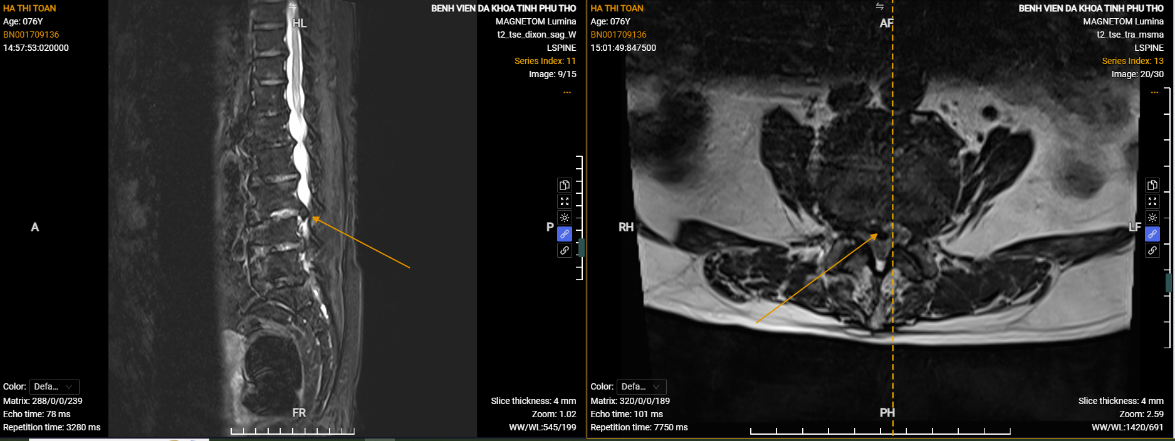

Hình ảnh phim chụp thể hiện vị trí thoát vị của người bệnh Hà Thị Toản.

Người bệnh bị thoát vị đĩa đệm tái phát sau khi điều trị tại một bệnh viện ở Hà Nội. Cơn đau có lúc khiến người bệnh không thể đi lại, phải nhờ người thân cõng. Lần này bệnh tái phát, gia đình quyết định đưa người bệnh đến Bệnh viện Đa khoa tỉnh Phú Thọ điều trị.

Sau phẫu thuật bằng kỹ thuật AUSS, người bệnh giảm đau hoàn toàn, bước đi vững và có thể vận động nhẹ nhàng.